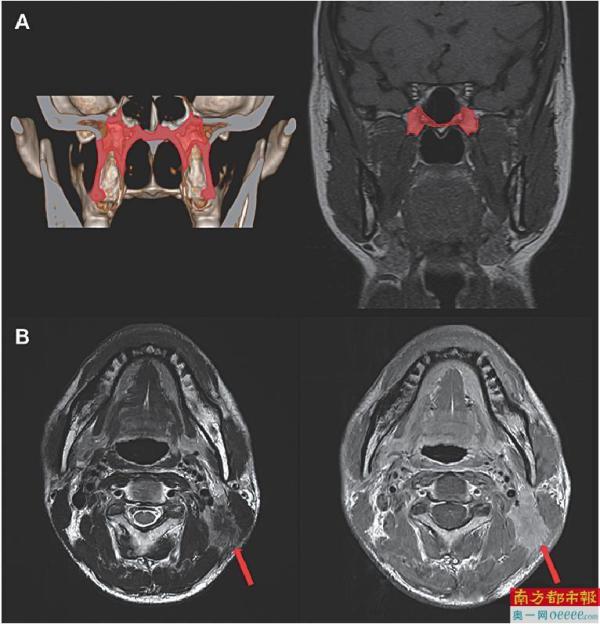

新版鼻咽癌解剖结构调整示意图。

随着核磁共振技术的发展,鼻咽癌早期颅底骨质受侵(仅翼突或蝶骨基底受侵)患者的检出率显著提高,占所有患者的10%-20%,原发灶分期为T3患者的20%-30%。既往研究报道早期颅底骨质受侵患者预后较好,或可豁免高强度的化疗。

本次研究结果显示,早期颅底骨质受侵的T3患者的5年生存率为91.9%,显著优于其余T3患者(88.8%),且与T2患者相似(91.5%)。因此,建议将轻度颅底骨质受侵降为T2。